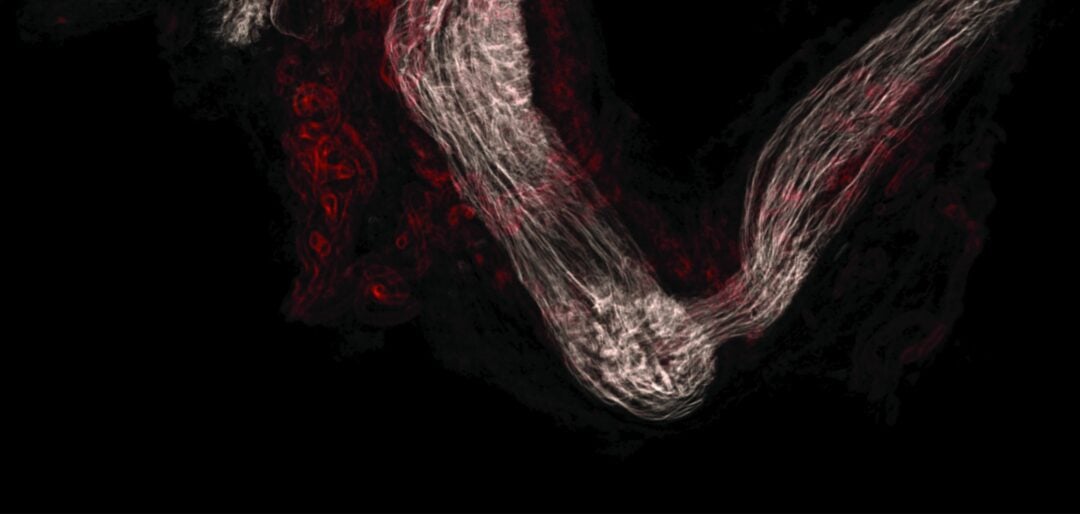

Peter Searson is leading a Johns Hopkins University team that is unravelling how Alzheimer’s and other diseases disrupt the blood-brain barrier, the complex interface that allows or blocks the passage of… Read More